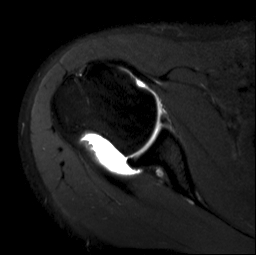

MRI

Hill Sachs variations